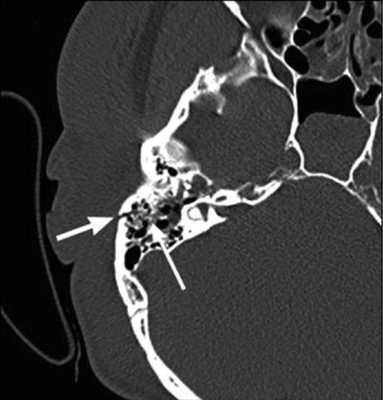

У 5 пациентов 1-й группы отмечалисьпосттравматические изменения височных костей (у 4 процесс носил односторонний характер, у 1 — двусторонний): у пациента с двусторонним поражением височных костей имели место разрыв и дислокация цепи слуховых косточек, изменений в структурах внутреннего уха выявлено не было. У остальных 4 был диагностирован поперечный перелом пирамиды височной кости: линия перелома проходила через область лабиринта и хорошо определялась на томограммах, при этом у одного из этих пациентов была обнаружена полная облитерация улитки, у другого был найден участок костной плотности в преддверии (давность травмы составила 25 и 8 лет соответственно).

Рис. 1. КТ, аксиальная проекция. Облитерация улитки (стрелка).

Рис. 2. МРТ, аксиальная проекция. Справа — полное отсутствие жидкости в улитке (короткая стрелка), слева — частичное (длинная стрелка).